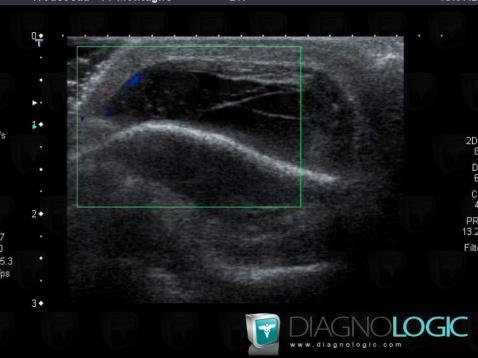

Bosse séro-sanguine, Tissus mous - Crâne, Echographie

- Diagnostic Bosse séro-sanguine (lié à Hématome), Localisation(s) Tissus mous - Crâne, comportant les gammes Masse kystique et pseudo kystique des parties molles